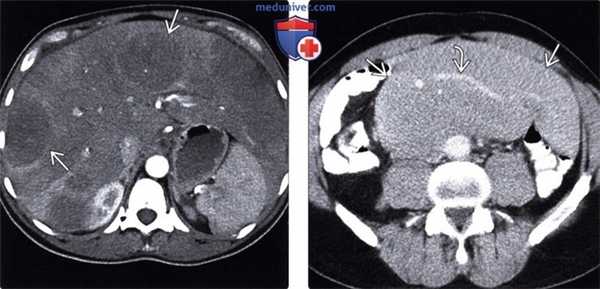

(Слева) При аксиальной КТ с контрастным усилением определяются гиподенсные мягкие ткани в виде «кожуры» вокруг обеих почек, классическое проявление периренальной лимфомы.

(Справа) При аксиальной КТ с контрастом определяется большое мягкотканное объемное образование вокруг правой почки, проявление периренальной НХЛ.

(Слева) При КТ с контрастным усилением в корональной плоскости визуализируется опухолевидное утолщение мягких тканей по краю подвздошной кишки. Обратите внимание на отсутствие обструкции кишки несмотря на значительное опухолевое поражение. Это характерное проявление лимфомы.

(Справа) На аксиальной КТ с контрастным усилением у ВИЧ-инфицированного пациента выявлено большое изъязвленное образование с наличием контраста в просвете тонкой кишки. Обратите внимание на типичное аневризматическое расширение просвета пораженной кишки вследствие опухолевой инфильтрации. Это часто встречающееся проявление лимфомы кишечника.

(Слева) При аксиальной КТ с контрастным усилением определяются множественные отдельно лежащие гиподенсные объемные образования в печени, а также выраженная диффузная инфильтрация большей части остальной паренхимы печени, выглядящей гиподенсной. При биопсии был подтвержден лимфоматозный характер инфильтрации.

(Справа) При аксиальной КТ с контрастом определяется большой конгломерат лимфатических узлов в брыжейке. Обратите внимание на сосуды внутри данного конгломерата, которые проходят сквозь него без сужения просвета или окклюзии, что является признаком, характерным для лимфомы.